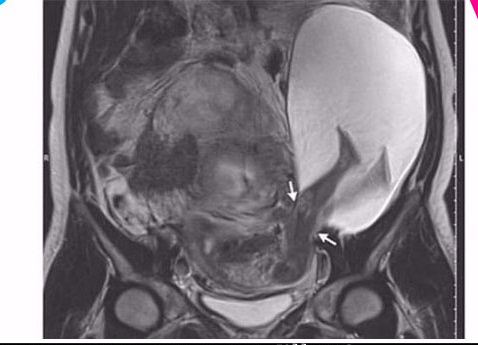

சீனாவில் கருவுற்று 35 வாரங்களே ஆன சிசு ஒன்று, தனது தாயின் கருப்பையை கால்களால் எட்டி உதைத்து வெளியே வந்துள்ளதால் அவசரமாக அறுவை சிகிச்சை செய்யப்பட்டு குழந்தை வெளியில் எடுக்கப்பட்டுள்ளது.

ஷான் என்ற பெண்மணி கர்ப்பமாக இருந்துள்ளார், 35 வாரங்களே ஆகியுள்ள நிலையில் இவருக்கு திடீரென பயங்கரமாக வயிற்றுவலி ஏற்பட்டுள்ளது.

சுமார் 5 மணிநேரமாக வயிற்று வலி தொடர்ந்து கொண்டே இருந்ததால் வைத்தியசாலைக்கு அழைத்துச் செல்லப்பட்டுள்ளார், ஷானை பரிசோதித்து பார்த்த வைத்தியர்கள் குழந்தையின் கால்கள் பெண்ணின் கருப்பையிலிருந்து வெளியே வந்து தாயினுடைய அடிவயிற்றில் ஊடுருவியபடி இருப்பதை அவதானித்துள்ளனர்.

குழந்தை தனது கால்களால் எட்டி உதைத்ததாலேயே தாய்க்கு தொடர்ந்து 5 மணிநேரமாக வயிற்று வலி ஏற்பட்டுள்ளது என தெரிவித்தனர்.

இதனைத் தொடர்ந்து அறுவை சிகிச்சை செய்து 10 நிமிடத்தில் பெண் குழந்தையை வைத்தியர்கள் வெளியே எடுத்துள்ளனர்.